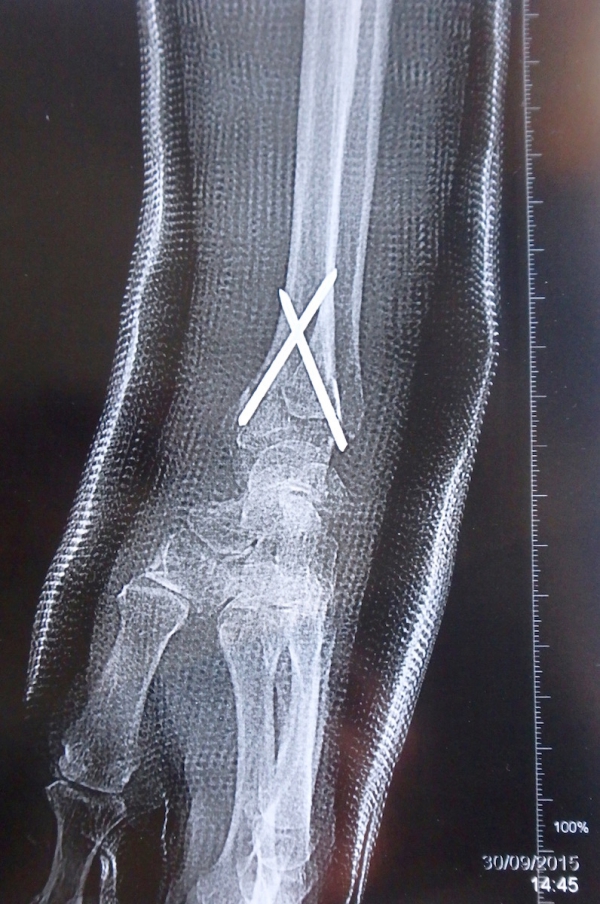

Radio du poignet de Simone le jour de son opération. On voit clairement les deux broches (Clinique de l’Europe, mercredi 30 septembre 2015).

Radio of Simone’s broken wrist (through the plaster) after her surgery operation. The two pins are cleary seen (30th September 2015).